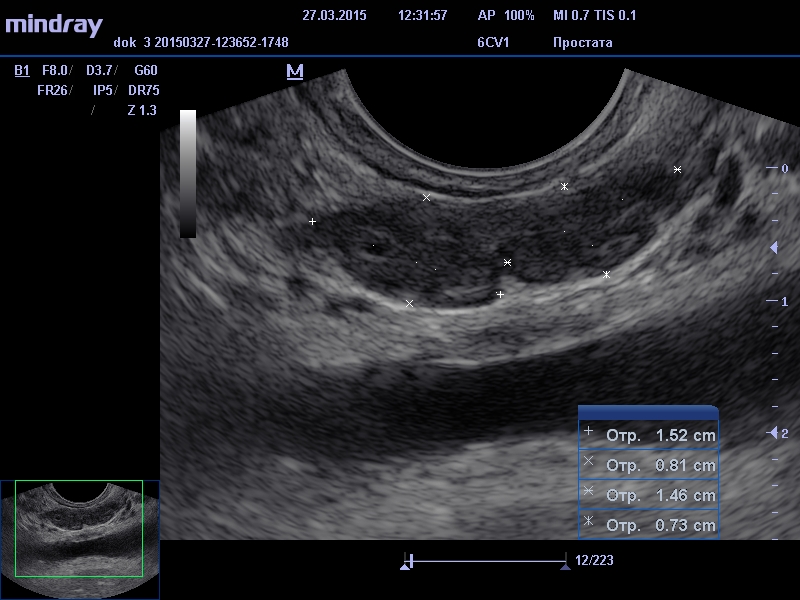

Этот способ диагностики имеет сокращенное название ТРУЗИ. Прибор, который вводится через анальное отверстие в прямую кишку, является ультразвуковым датчиком. Этот прибор очень чувствительный и благодаря ему врач, который проводит исследование, может видеть в органе малейшие отклонения от нормы, не видимые при трансабдоминальном способе исследования. При проведении исследования этим способом простату от датчика отделяет только стенка прямой кишки.

При проведении диагностики простаты мы определяем, какую форму и структуру имеет орган, и какой у него размер. Определение всех этих параметров входит в единую стоимость диагностики. Ультразвуковой современный и высокотехнологичный датчик выводит данные на экран, на котором видна реальная картина, исследуемого органа.